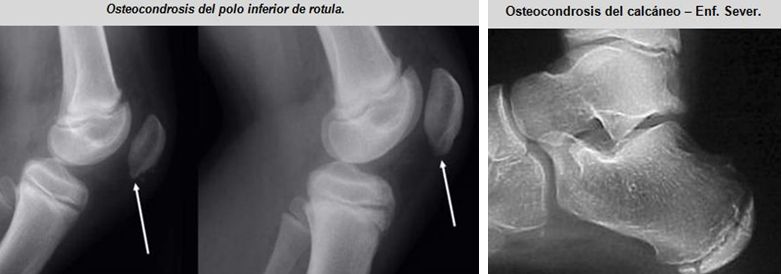

Alguna de ellas son: la enfermedad de Sinding-Larsen-Johansson, la enfermedad de Osgood-Schlatter, y la enfermedad de Sever; son osteocondrosis en las apófisis del poloinferior de la rótula, la tibia proximal, y el calcáneo, respectivamente.

Esta apofisitis por tracción se desarrolla debido a la fuerza del tendón rotuliano en el polo inferior de la rótula. A diferencia de OSD, SLJ parece tener una predilección por los varones más que por las mujeres, y se observa en adolescentes activas entre las edades de 10 y 13 años. Debido a su madurez esquelética más temprana, las mujeres se ven afectadas a una edad más joven en comparación con los varones.

El síndrome de Sinding-Larsen-Johansson tiene una patogenia similar a la de la enfermedad de Osgood-Schlatter y los dos trastornos a veces se producen al mismo tiempo. El síndrome de Sinding-Larsen-Johansson es causado por el aumento de la tensión y de presión, debido a la tracción repetitiva por el tendón rotuliano en el polo inferior de la rótula (todavía en parte cartilaginosa en adolescentes) durante la contracción de los músculos cuádriceps.

Esto conduce a daños en los cartílagos, la hinchazón y el dolor, especialmente después de un esfuerzo excesivo, y más tarde al engrosamientodel tendón y la fragmentación del polo inferior de la rótula, y en ocasiones la inflamación de la bursa, situada entre el tendón y la rótula.

Las radiografías pueden demostrar calcificación irregular en el polo inferior de la rótula o pueden ser normales, especialmente en un paciente más joven que aún puede no tener una apófisis visible presente en la radiografía. Por lo tanto, los hallazgos de la historia y examen físico clásicos pueden, y deben, ser utilizados para hacer el diagnóstico, con las radiografías reservadas para casos atípicos u otras características relativas.

Así se denomina a la inflamación de la epífisis posterior del calcáneo. Comienza de forma insidiosa y afecta más a niños entre los 10 y 15 años. Provoca cojera, molestias en el talón y en ocasiones tumefacción. Es la causa mas frecuente de talalgia en niños y adolescentes.

Enfermedad de Server o apofisitis del calcáneo, es una causa común de dolor de talón en los atletas jóvenes. El tendón de Aquiles ejerce fuerzas de tracción en la apófisis del calcáneo con la actividad física. La mayoría de los pacientes asocian sus síntomas con un deporte en particular, el fútbol es el más común. Los síntomas son peores en el comienzo de una nueva temporada de deportes o durante un brote de crecimiento. La actividad de levantamiento de peso y los zapatos, especialmente zapatos de fútbol, pueden agravar los síntomas.

Las radiografías simples se ven normales.

En la radiografía se aprecia aumento de la densidad y fragmentación de la epífisis posterior del calcáneo. Sin embargo, esta imagen también es compatible con la normalidad, por lo que el diagnóstico de esta enfermedad es siempre clínico. La presión con los dedos en la parte posterior del talón provoca dolor.